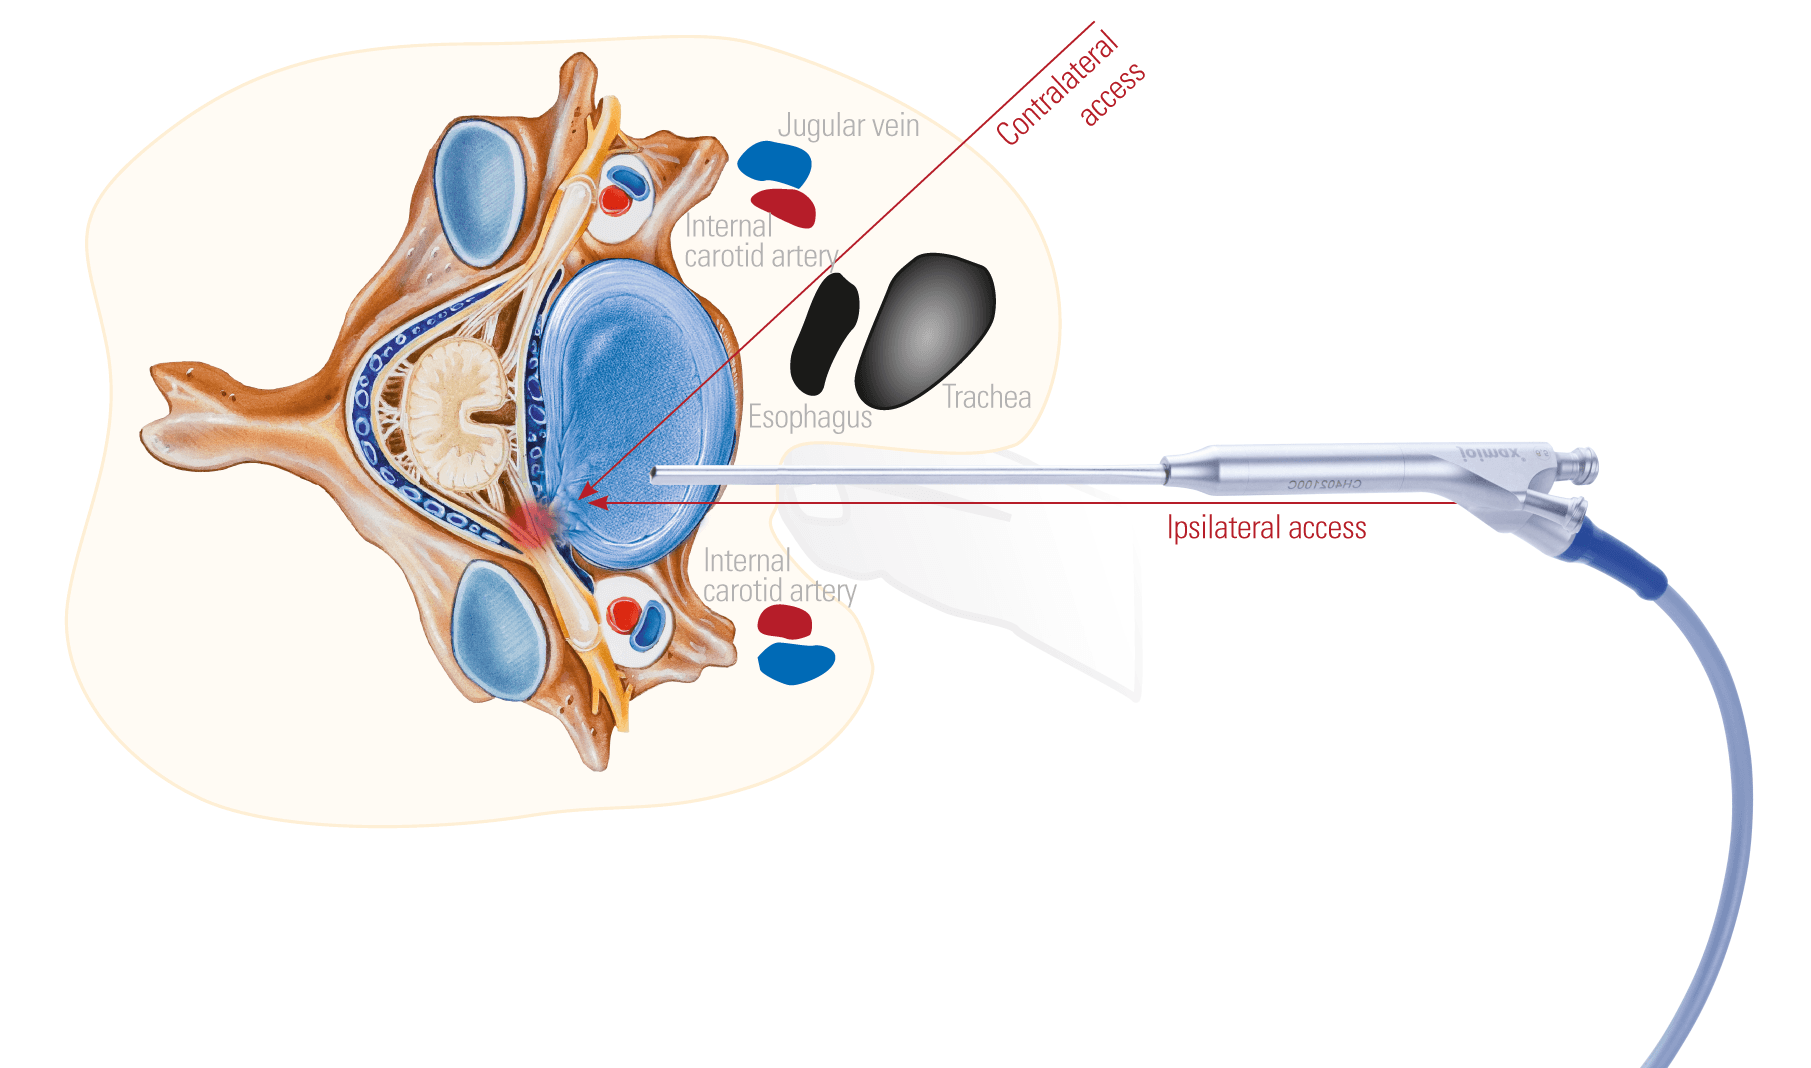

Founded in 2001, Joimax is a leading German medical technology company specializing in the development of innovative, minimally invasive solutions for spinal surgery.

Recognized for its advanced endoscopic systems and precision surgical instruments, Joimax is committed to improving patient outcomes by enabling less invasive procedures that reduce recovery times, minimize incisions, and limit trauma to surrounding tissues.Products from